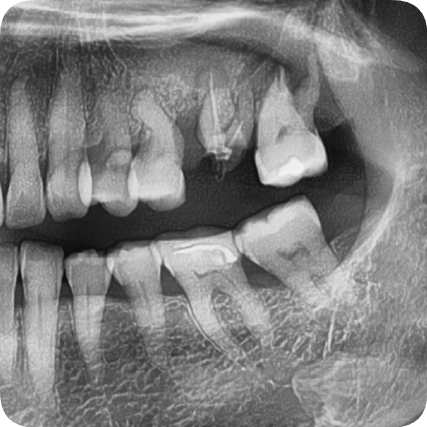

처음 내원 한 당시

서울오브치과병원에서는 모든 임플란트 치료 전에

3D CT를 촬영합니다.

이번 케이스에서는

#26, #27 주변의 심한 골소실

상악동이 매우 낮아진 상태

치근과 잇몸 사이의 염증

이 확인되었습니다.

파노라마 엑스레이와 구강내 사진을 통해 확인한 결과,

왼쪽 위 두 개의 어금니가 파절 및 결손 상태

주변 치조골은 비교적 건강하여 뼈이식이

최소화된 상태에서도 임플란트 식립 가능

이라는 진단을 내렸습니다.